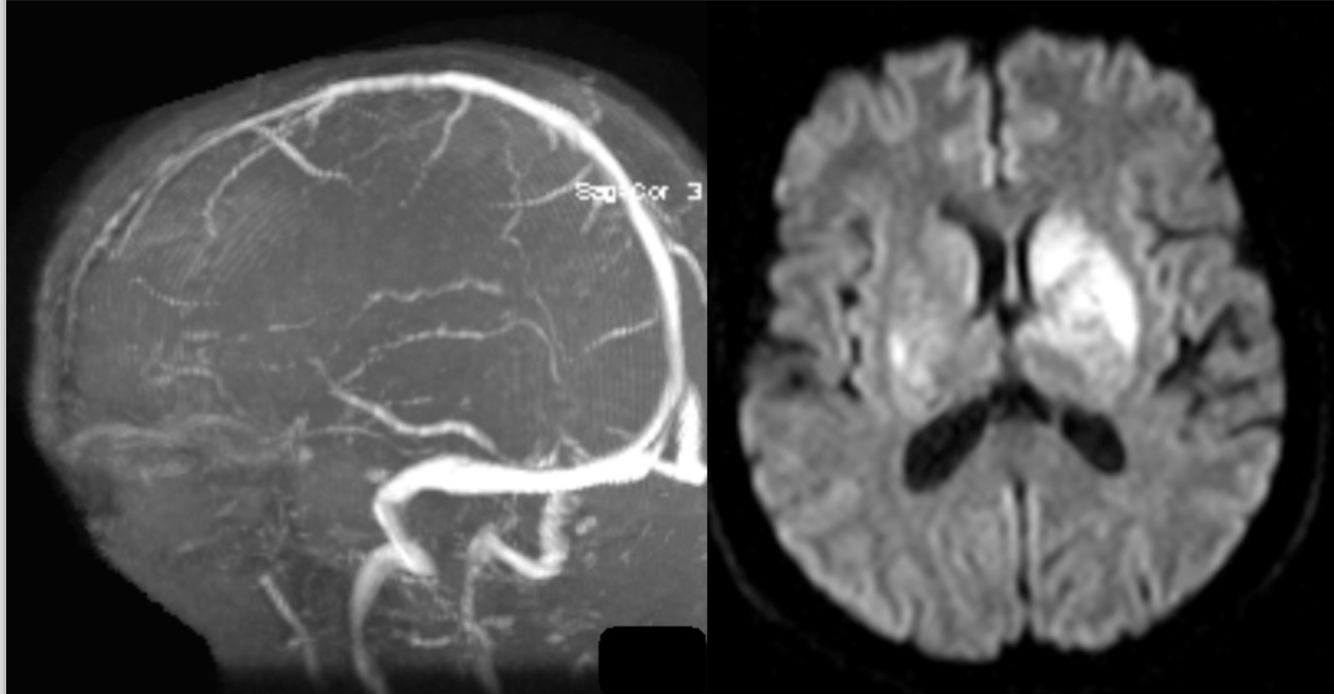

35 y/o F with acute R-sided weakness.

Thrombosis of inferior sagittal sinus